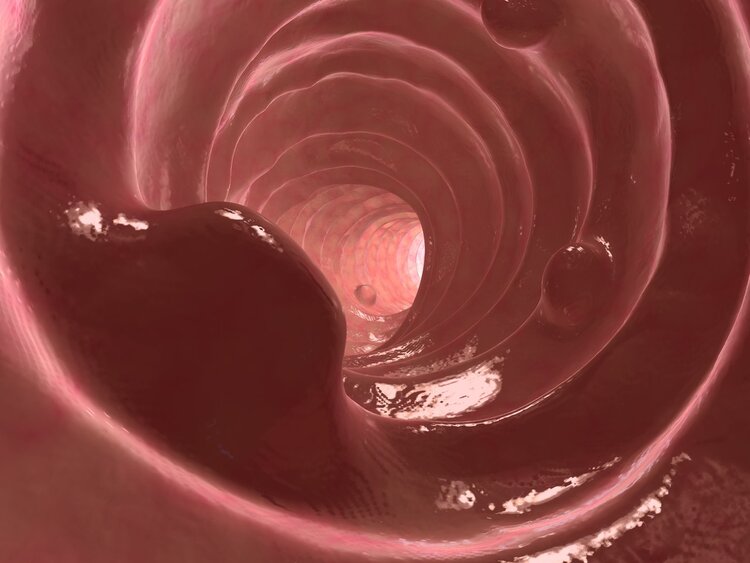

肠息肉是在肠黏膜局部增生而形成的赘生物 , 简单来说就是在大肠内腔粘膜表面多生长出来的一块肉 。

息肉癌变只需要4步:小息肉——大息肉——高级别上皮内瘤变——息肉癌变 。 值得警惕的是 , 我国的肠息肉的发病率还是比较高的 , 在人群中的总发病率高达1.6%~12.0% , 特别是中年后的发病率更高 , 能达到10%~30% 。